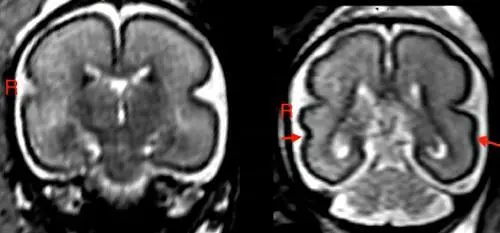

孕期饮酒会改变婴儿大脑结构